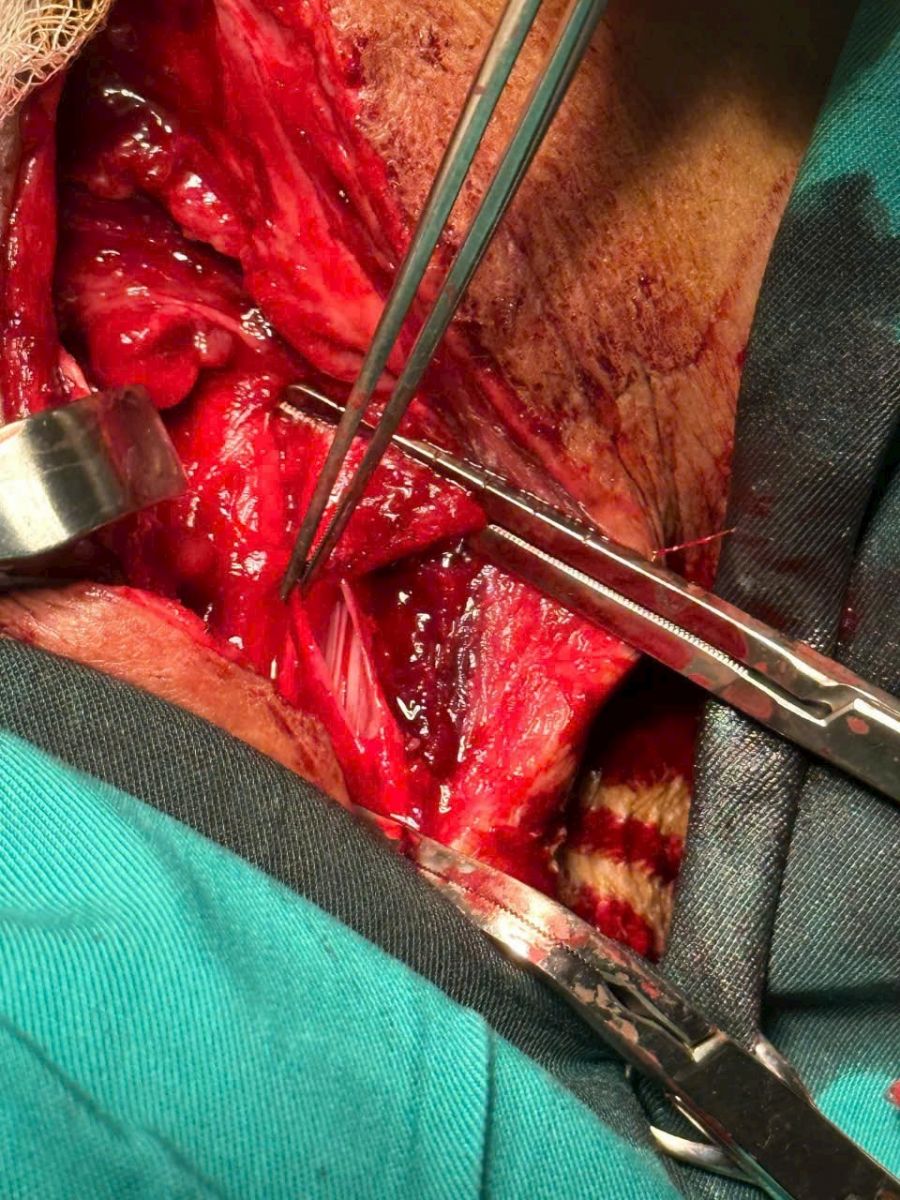

Sau khi hội chẩn, các bác sỹ nhận định đây là trường hợp có vết thương vùng cổ phức tạp, đứt tĩnh mạch cảnh, vết thương khí quản (1/3 dưới), đứt động mạch giáp dưới và rách màng phổi phía đỉnh phổi…; chuyển mổ cấp cứu cho bệnh nhân.

Vết thương vùng cổ phức tạp, đứt tĩnh mạch cảnh...

Bác sỹ CKI Nguyễn Tiến Độ - Khoa Ngoại tổng hợp, BVĐK tỉnh - người trực tiếp phẫu thuật cho bệnh nhân T. cho biết: "Đây là ca bệnh rất nguy kịch, máu chảy nhanh, ồ ạt, bệnh nhân bị sốc, mất máu nặng, có thể tử vong ngay lập tức. Vết thương tĩnh mạch cảnh là vết thương mạch máu lớn, nếu không xử trí kịp thời thì sẽ dẫn đến mất máu nhanh và tử vong... Chính vì vậy, đòi hỏi bác sỹ phải thao tác quyết đoán, chính xác. Ưu tiên lớn nhất là việc xử lý vết thương tĩnh mạch cảnh nên chúng tôi đã tiến hành cầm máu và khâu nối tĩnh mạch cảnh, sau đó, khâu màng phổi rồi tiếp tục tiến hành xử lý vết thương ở khí quản.